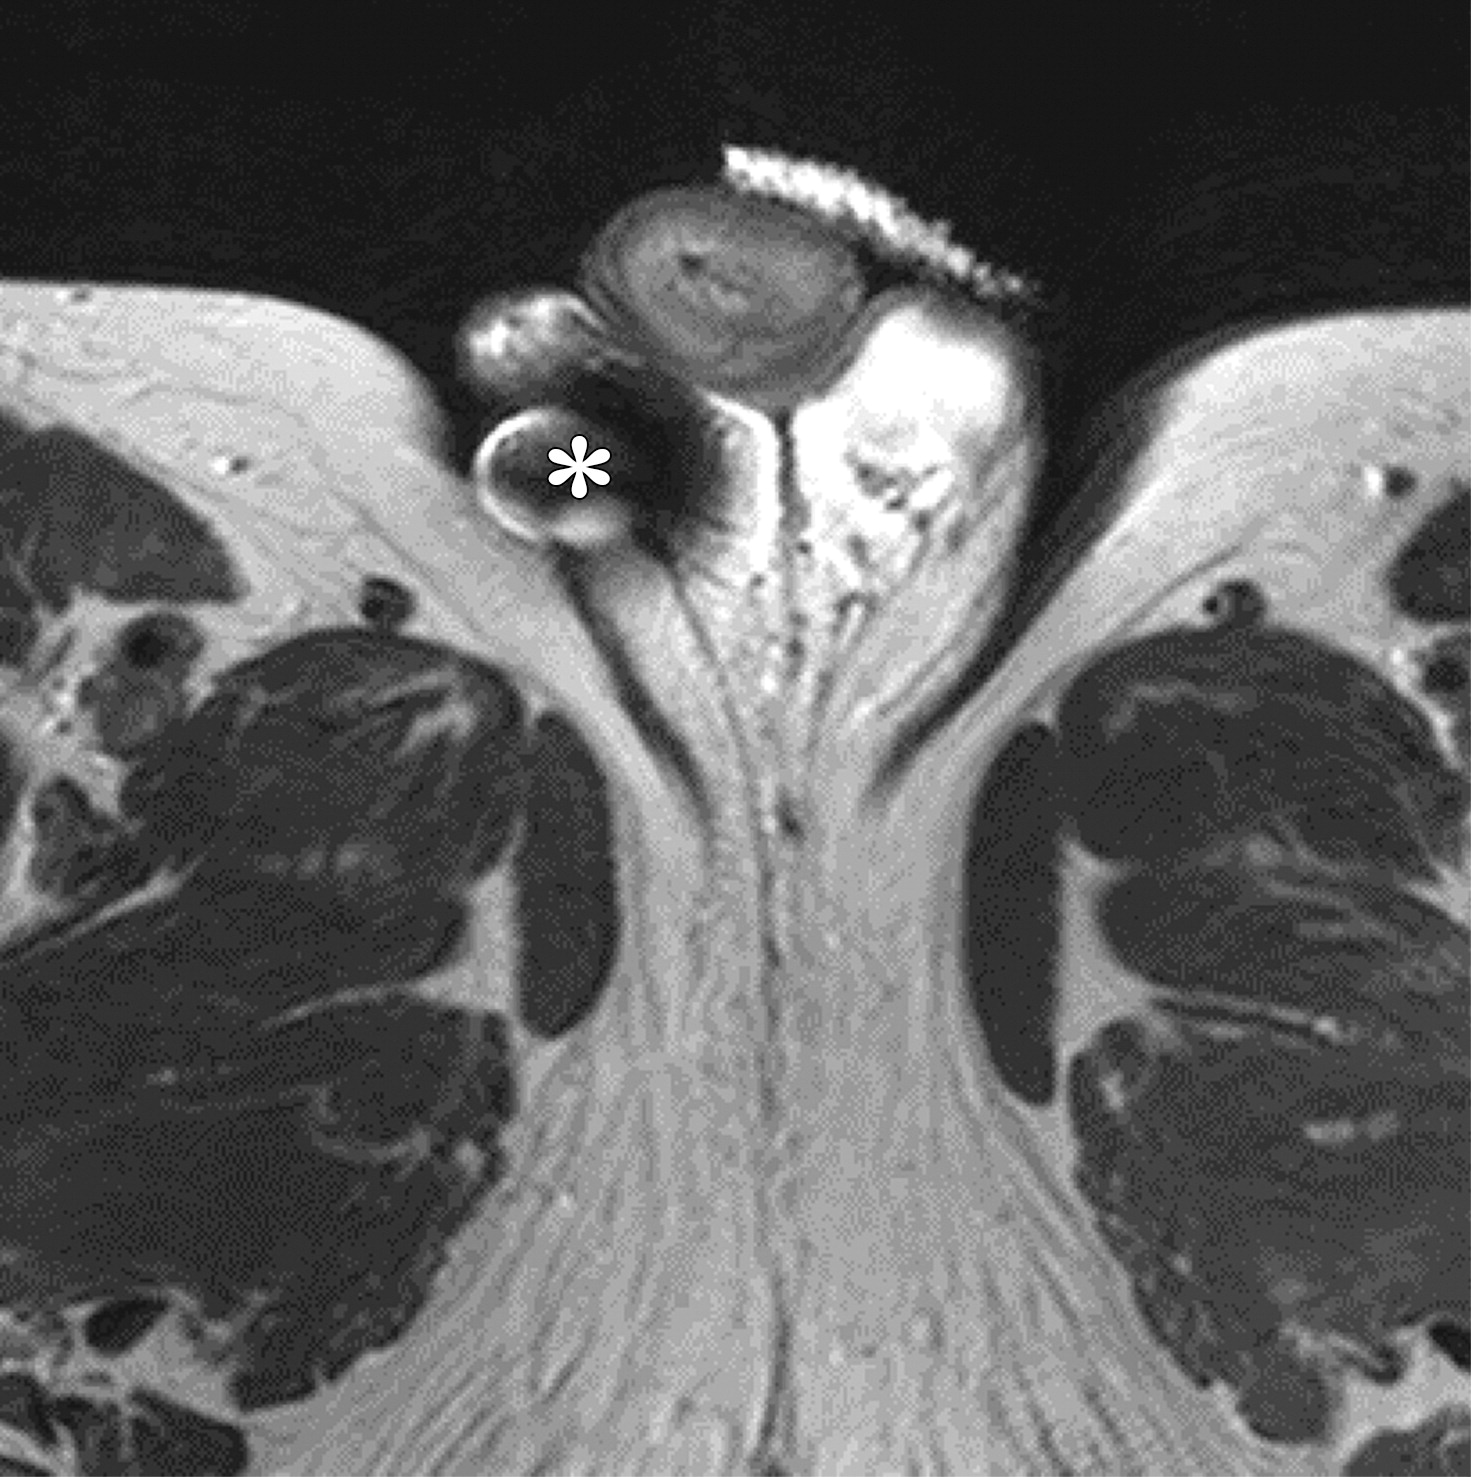

人工尿道括约肌。

人工尿道括约肌的组成部分包括位于腹部的压力容器(a图中白色长箭头),围绕球部尿道的括约肌袖口(b图中白色短箭头),以及位于阴囊的泵(c图中白色*)。